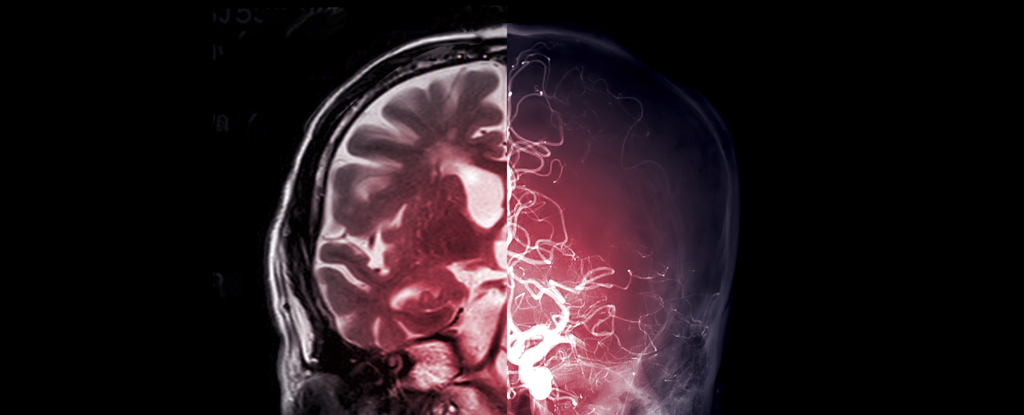

A groundbreaking study led by researchers at Monash University's Turner Institute for Brain and Mental Health has challenged the century-old belief that complex neural connectivity is the primary determinant of brain function. Using MRI scans and the principle of eigenmodes, the study found that the overall shape of an individual's brain has a more significant impact on cognitive processes, emotions, and behavior than previously thought. The findings offer new avenues for understanding brain function and disease, simplifying the study of how the brain functions, develops, and ages. The research team discovered a previously unappreciated relationship between brain shape and activity, highlighting the potential to predict brain function directly from its shape and explore individual differences in behavior and risk for psychiatric and neurological diseases.